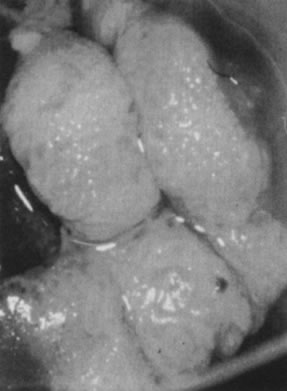

Other HPV-associated lesions of the vulva consist of papillary changes commonly visible with the naked eye but best appreciated colposcopically. The papillae are multiple, small villous projections from mucous membranes that may involve the entire vestibule and inner surface of the labia minora. When extensive, the papillary changes are referred to as micropapillomatosis vestibularis or labialis (Fig. 19). Some women with vestibular papillae have intense vulvar pain (vulvodynia), burning, irritation, and pruritus. Although the papillary formations have been associated with various HPV types, especially HPV-6, they frequently represent anatomic variants of vestibular mucosa.76 It is unlikely that HPV infections are responsible for vulvodynia, but overly aggressive therapy directed against vulvar or vaginal HPV-associated lesions may result in damage to the vulvar epithelium and chronic vulvar pain.

Fig. 19. Colpomicrograph of micropapillomatosis vestibularis. The entire vestibule is covered with myriad small villous projections. The epithelium tested negative for HPV.

Histologically, isolated papillary fronds are observed, with prominent fibrovascular cores associated with chronic inflammation and dilated capillaries. Koilocytotic transformation of superficial epithelial cells is variable.